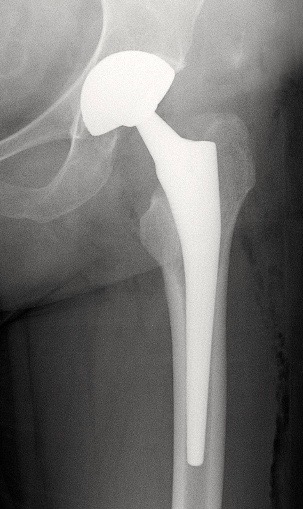

2. PTH

INDICATIONS:

• Arthrose (N°1)

• ONA

• Dysplasie

• Fracture du col

- Scellées avec du ciment chirurgical, ou recouverte d’hydroxyapatite (intégration à l’os)

- Couple de frottement: métal, céramique ou polyéthylène

- Tiges longues ou courtes

- Double mobilité: un insert entre la tête et la cupule